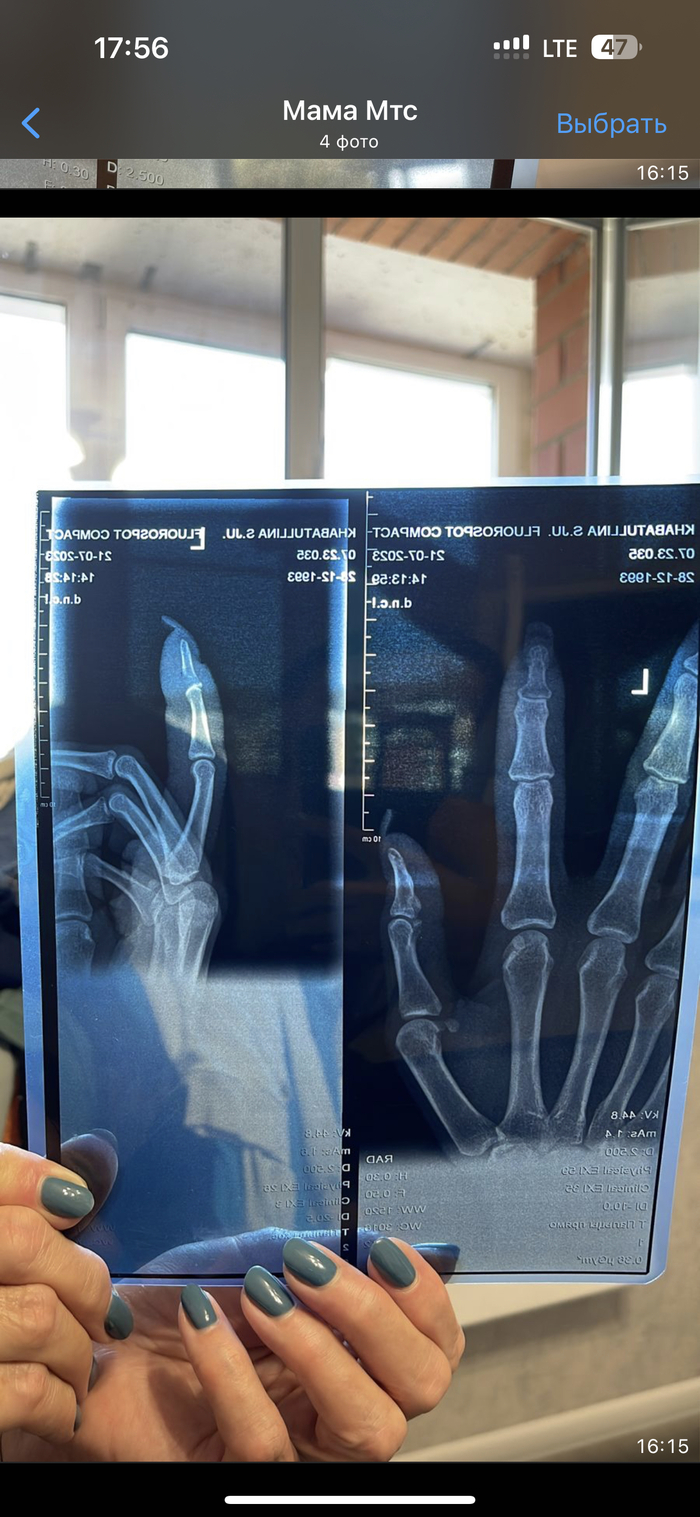

Срочно нужна помощь в Спб или Москве

Здравствуйте! Работаю у вас в области, недавно у младшей сестренки случился инцидент. Ездила отдыхать на Алтай со своим котом. Он сбежал, нашли его в подвале, когда она пыталась его взять он ее укусил за палец. Пошло заражение. В больнице в Иркутске (она там проживает, но сейчас вылетает в питер) сказали что нужно прийти на артем через пару недель, отек сам спадет. На приеме сказали что пошло заражение, нужно отрезать палец по фалангу. Девочка в истерике, скромная и добрая. Проконсультировались час назад с первым врачом с Питера до кого все таки смогли достучатся, сказал что шансы спасти палец есть, но не обещает. Есть снимки , могу отправить. Подскажите люди добрые пожалуйста, есть ли может у кого опыт? Может кто то сможет принять? Это моя сестричка и не могу найти себе места🥺 она мне дорога. Времени мало, через два три дня говорят что пойдет заражение уже на кисть. Прошу помощи 🙏 в обычном штатном режиме записаться иногороднему тем более не знающему города, большая потеря времени, которого остается все меньше. Может есть номера или среди Вас есть человек который может помочь. Пост без рейтинга. Пикабу, первый раз прошу помощи, помощи не для себя, но очень сильно рассчитываю

Показать полностью 4